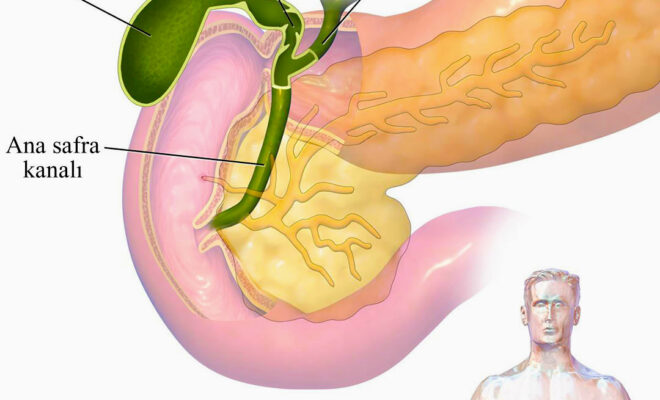

Анатомия и особенности Гартманова кармана желчного пузыря